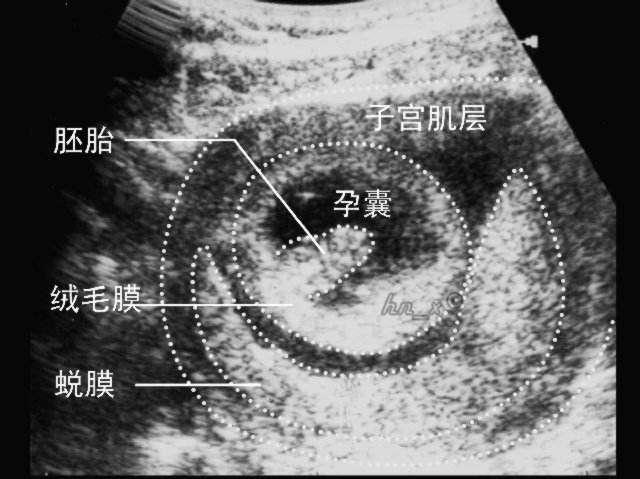

2. B超检查

当然,除了验血,也有的医生可能会让做B超检查,但也可能因为天数太少,医生会给开阴超检查,相比来说,阴超要比腹部B超看的更清楚些。

这个阶段,医生会重点看 孕囊(一般是在孕30-40天孕囊出现),医生会根据“孕囊的大小、位置、性状”等,来判断胚胎是否在正常发育。

① 孕囊大小

这里说的“孕囊大小”,指的是孕囊的直径,在怀孕6周时孕囊的直径约为2cm。

② 孕囊形状和位置

不少人,在怀孕早期会根据孕囊的性状来判断怀的男孩还是女孩,其实这是没科学道理的,不过在这个阶段,的确可以通过B超看孕囊的性状是“椭圆形还是圆形”,而医生会根据孕囊的性状、位置等判断胎儿的发育情况。